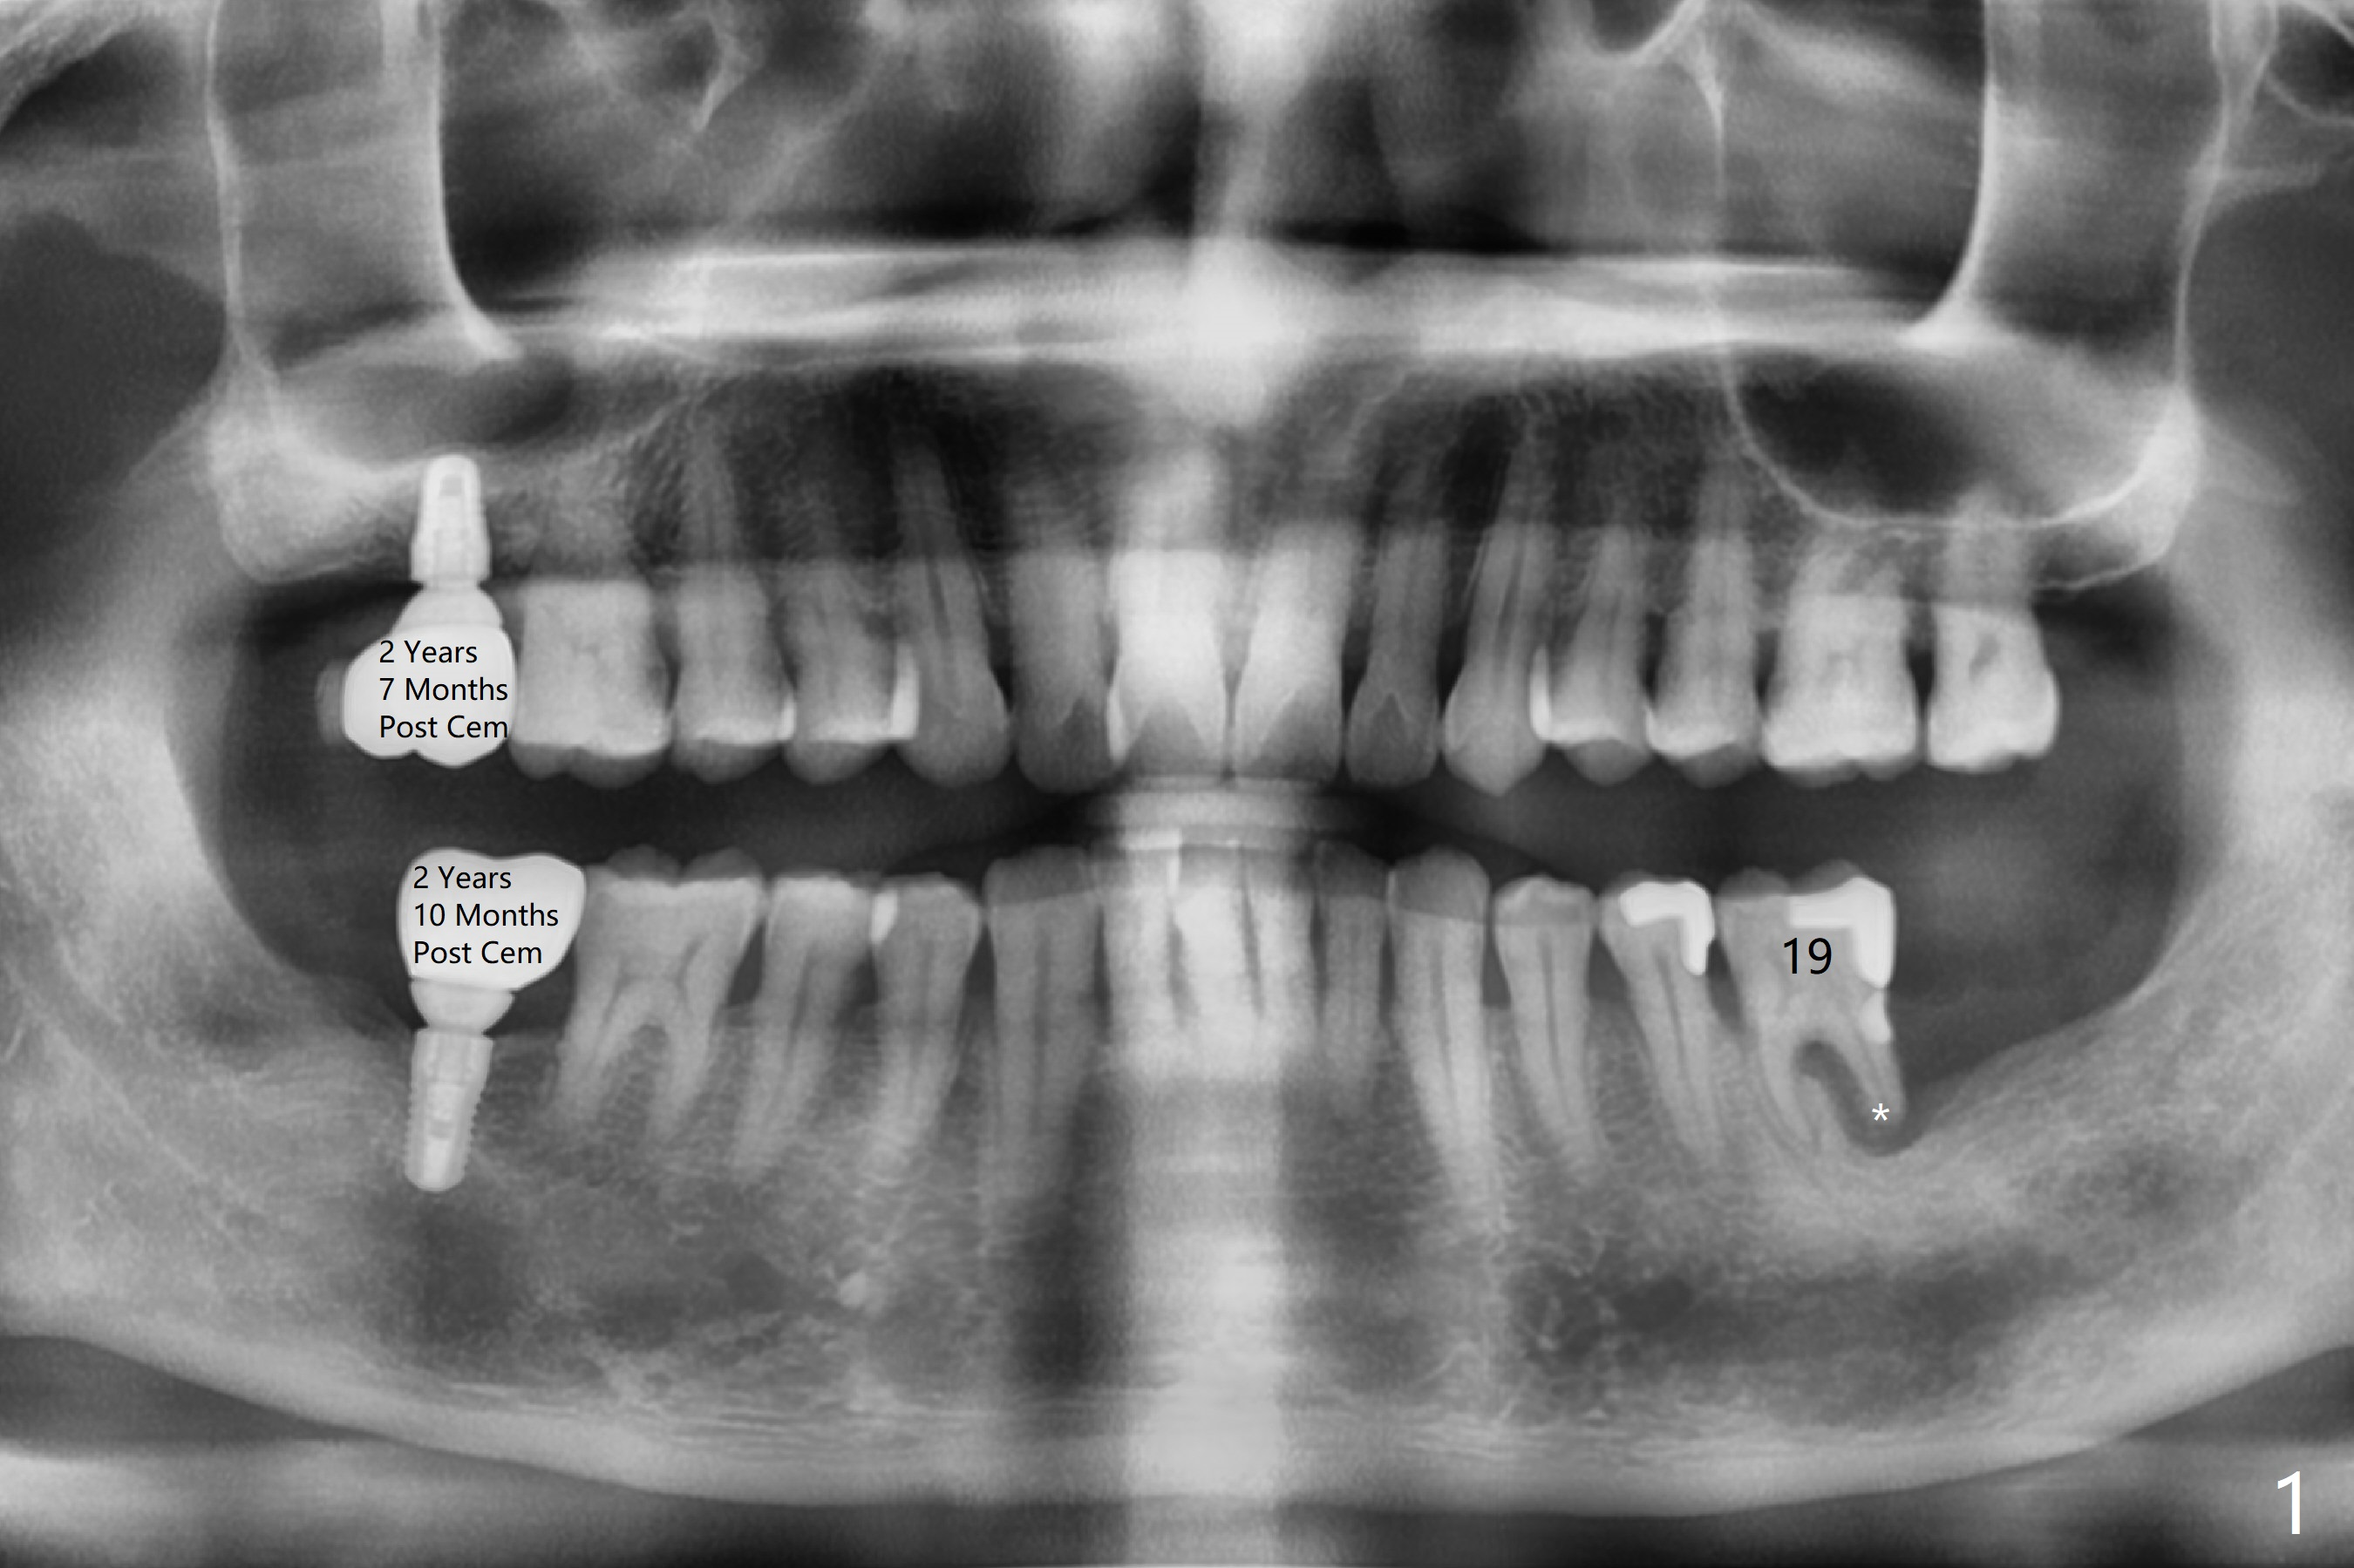

A 49-year-old man agrees to have #19 extracted for implant, 2 years 7 months and 2 years 10 months post cementation at #2 and 31, respectively (Fig.1). Because of severe bone loss in the distal socket of #19, a 4.5x10 mm implant will be placed in the mesial one (Fig.2). To reduce the chance of blockage of blood supply to the tooth #20 (Fig.3 red curved line), the implant will be not placed deep. After osteotomy with guide, a 1.5 mm longer implant will be chosen if there is extra coronal bone as shown in Fig.3 (3D image (white line)).